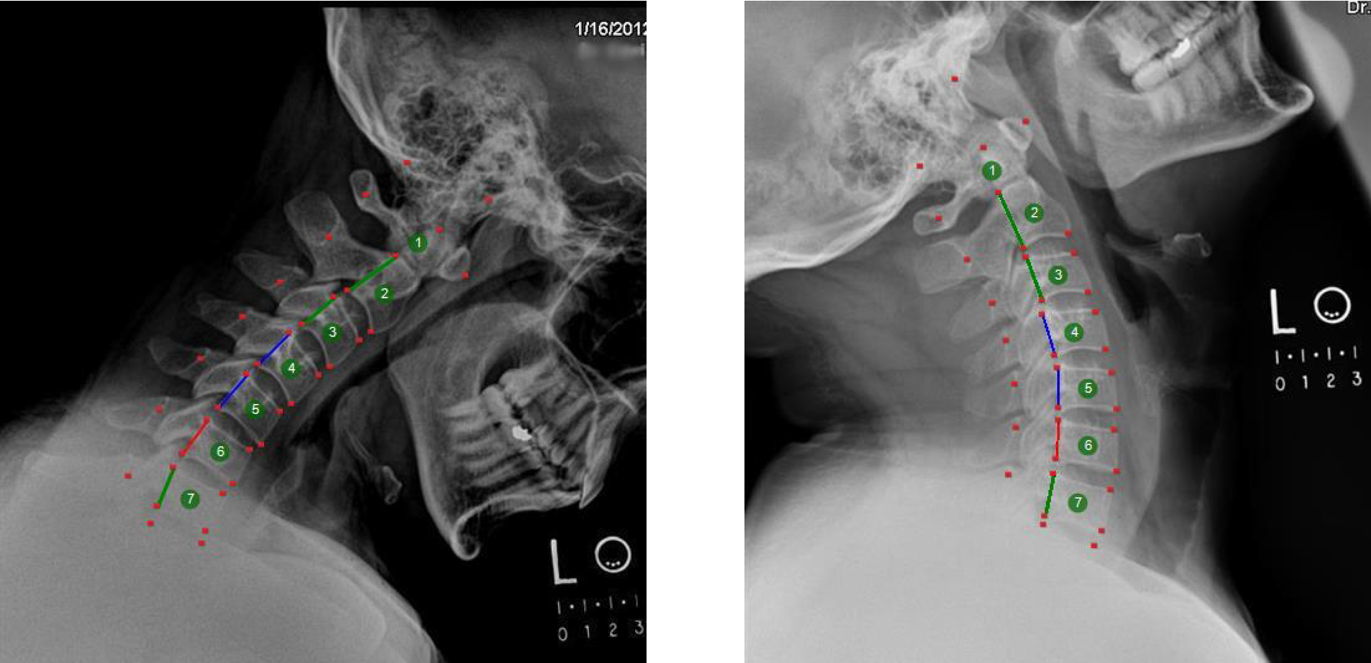

Report of Findings, X-ray Analysis, Posture, ROM, and EHR Documentation Software

AOMSI, Ligament Analysis Software and service